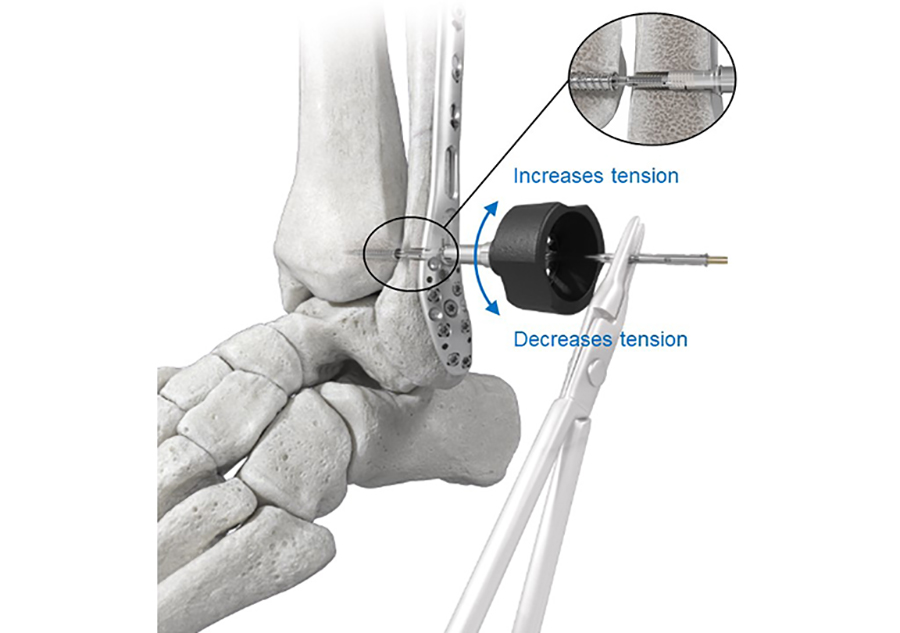

The Tensioning Knob is used to fine tune and readjust the tension in the Suture Bridge intraoperatively (Fig 3). Clockwise or counterclockwise rotation of the Tensioning Knob will advance or reverse the Fibula Tensioning Cap, thereby adjusting the tension in the suture bridge in a two-way tension control to achieve the desired level of correction.

The implant is a multicomponent anchor system consisting of four main components (Fig 1):

- Fibula Tensioning Cap: interfaces with the Fibula Link. A rotation of the Tensioning Cap applies tension to the construct.

- Fibula Link: transfers the tension applied by the Fibula Tensioning Cap to the Suture Bridge. As such, it functions as an interface in the primary tension mechanism.

- Suture Bridge: applies compression between the fibula and the tibia via transferring the tension between the Fibula Link and the Tibia Screw. The 4 mm long Suture Bridge consists of four strands of #1 Ultra High Molecular Weight Polyethylene.

- Tibia Screw: functions as an anchor in the tibia.